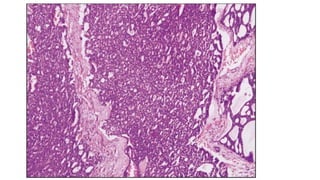

• Basal cell adenocarcinoma: Low grade malignant counterpart of basal cell

adenoma

Resembles basaloid (cloacogenic) carcinoma of anal canal or upper

aerodigestive tract

Also called basaloid carcinoma

Similarity with ACC:

infiltrative with perineurial invasion

Differentiating with ACC:

absence of peripheral palisading nuclei, lack of continuity with

epidermis/hair sheath, negative to CEA, S-100, Amylase.

• Basal celladenocarcinoma: Low grade malignant counterpart of basal cell adenoma Resembles basaloid (cloacogenic) carcinoma of anal canal or upper aerodigestive tract Also called basaloid carcinoma Similarity with ACC: infiltrative with perineurial invasion Differentiating with ACC: absence of peripheral palisading nuclei, lack of continuity with epidermis/hair sheath, negative to CEA, S-100, Amylase.